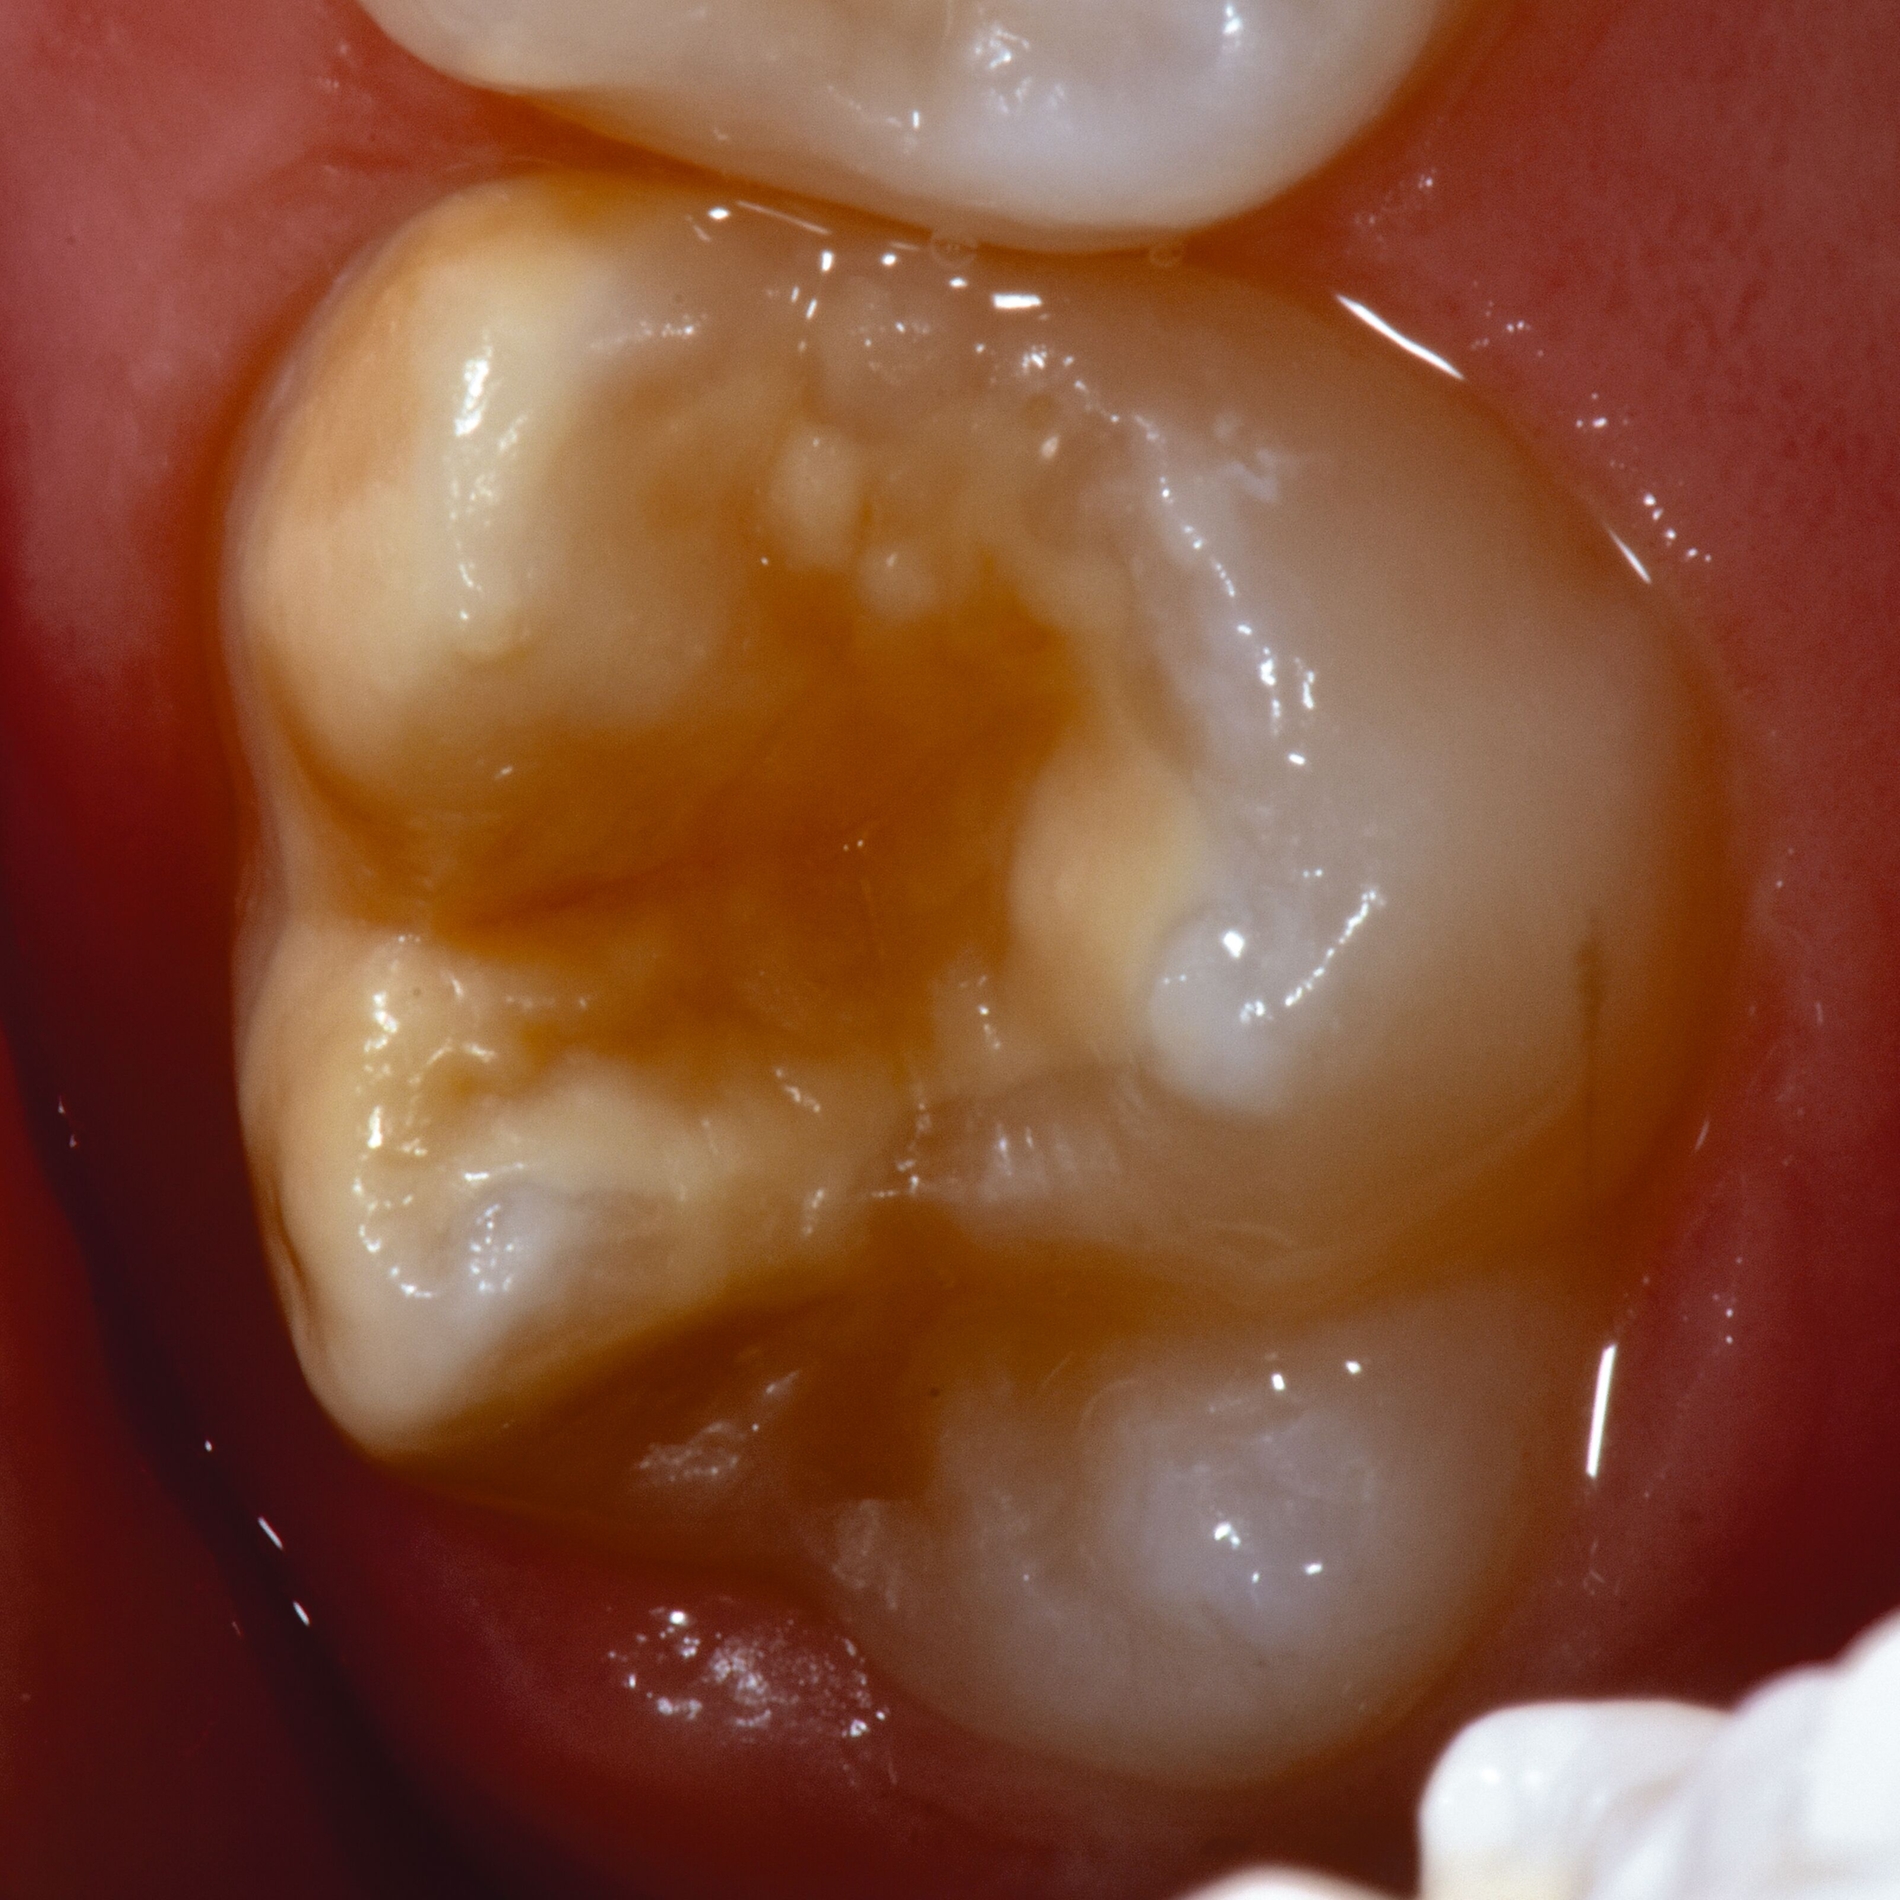

Bei post- beziehungsweise präeruptiven Oberflächendefekten ergibt sich in einigen Fällen die Indikation zur Restauration dieser MIH-Zähne. Unter Verweis auf die Lokalisation von MIH-bedingten Hypomineralisationen außerhalb der typischen Kariesprädilektionsstellen – zum Beispiel okklusale Fissuren und Grübchen oder Approximalflächen – werden diese als „atypische Restaurationen“ (engl.: „atypical restoration“, Abbildung 6) klassifiziert. Als ein weiteres Erkennungsmerkmal gilt die Präsenz von Hypomineralisationen im Bereich der Restaurationsränder. MIH- und kariesbedingte Restaurationen können und sollten sicher voneinander abgegrenzt werden.

Für die Dokumentation und Klassifikation der MIH wurden verschiedene Systeme vorgeschlagen. Als historisch und veraltet gilt der (modifizierte) DDE-Index. Demgegenüber haben die Kriterien der EAPD – abgegrenzte Opazitäten (Abbildung 3 und 4), Schmelzeinbrüche (Abbildung 5), atypische Restaurationen (Abbildung 6) – mittlerweile die weiteste Verbreitung gefunden. Diese wurden 2003 erstmals zur Beschreibung der MIH auf empirischer Basis publiziert [Weerheijm et al., 2003] und den Jahren 2010 und 2022 im Rahmen der damaligen MIH-Workshops bestätigt [Lygidakis et al., 2010; 2022].